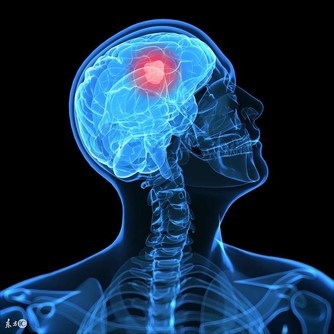

1. 癌症只是一種疾病

實際上,目前我們已經發現了數百種癌症,每個都具有獨特的分子特徵和可變的臨床表達。比如,在神經腫瘤學中,已經確定了至少120種腦和脊髓癌亞型。對於這種多樣化的敵人,我們的診斷和治療方法必須擴大,也必然很難。